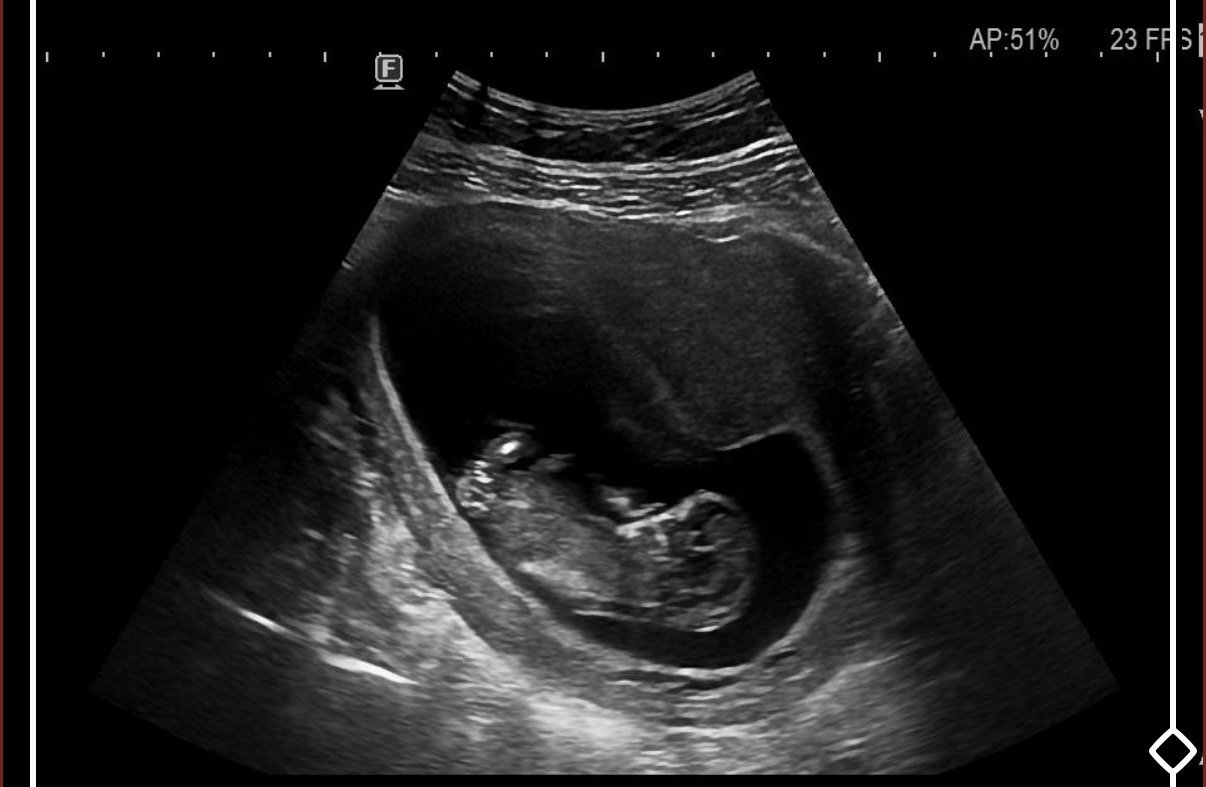

Benim kese böyleydi oğlum oldu ama bilemiyorum rabbim sağlıkla mutlulukla versin inşallah

Kız bu erkege çok benziyor hakkında hayırlısı olsun sağlıkla kucağına almayı nasip etsin

Kız iki çizgi var

cinsel organı düz 80 derece aşağına bence kız

Bence erkekkk

Benim keseme benziyor bence erkek